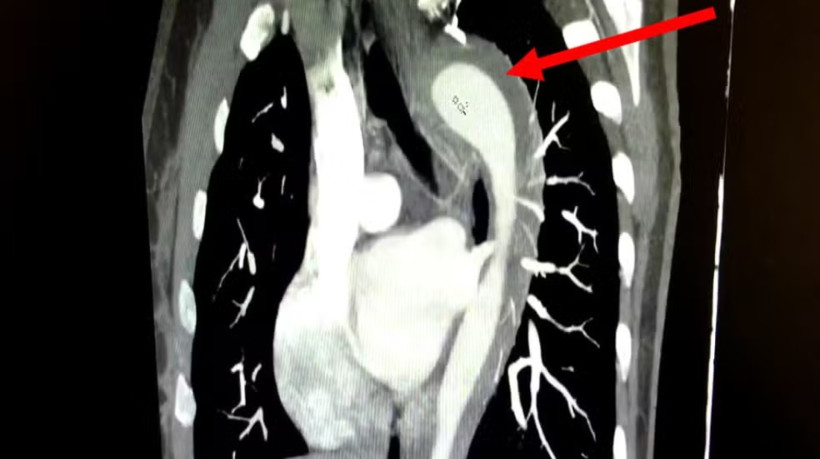

Os médicos responsáveis identificaram fatores de risco importantes no histórico da paciente: hipertensão arterial não tratada há um ano e tabagismo crônico com 17 anos de duração. Exames de imagem confirmaram a presença de um hematoma intramural na aorta — um acúmulo de sangue dentro da parede do maior vaso sanguíneo do corpo, que pode levar à ruptura total da artéria.

O hematoma intramural é uma das manifestações da Síndrome Aórtica Aguda, condição que apresenta alta taxa de mortalidade e pode evoluir rapidamente para aneurisma ou ruptura completa da aorta. Estima-se que a mortalidade aumente 1% a cada hora sem tratamento e que cerca de 22% dos casos sequer sejam diagnosticados antes da morte.